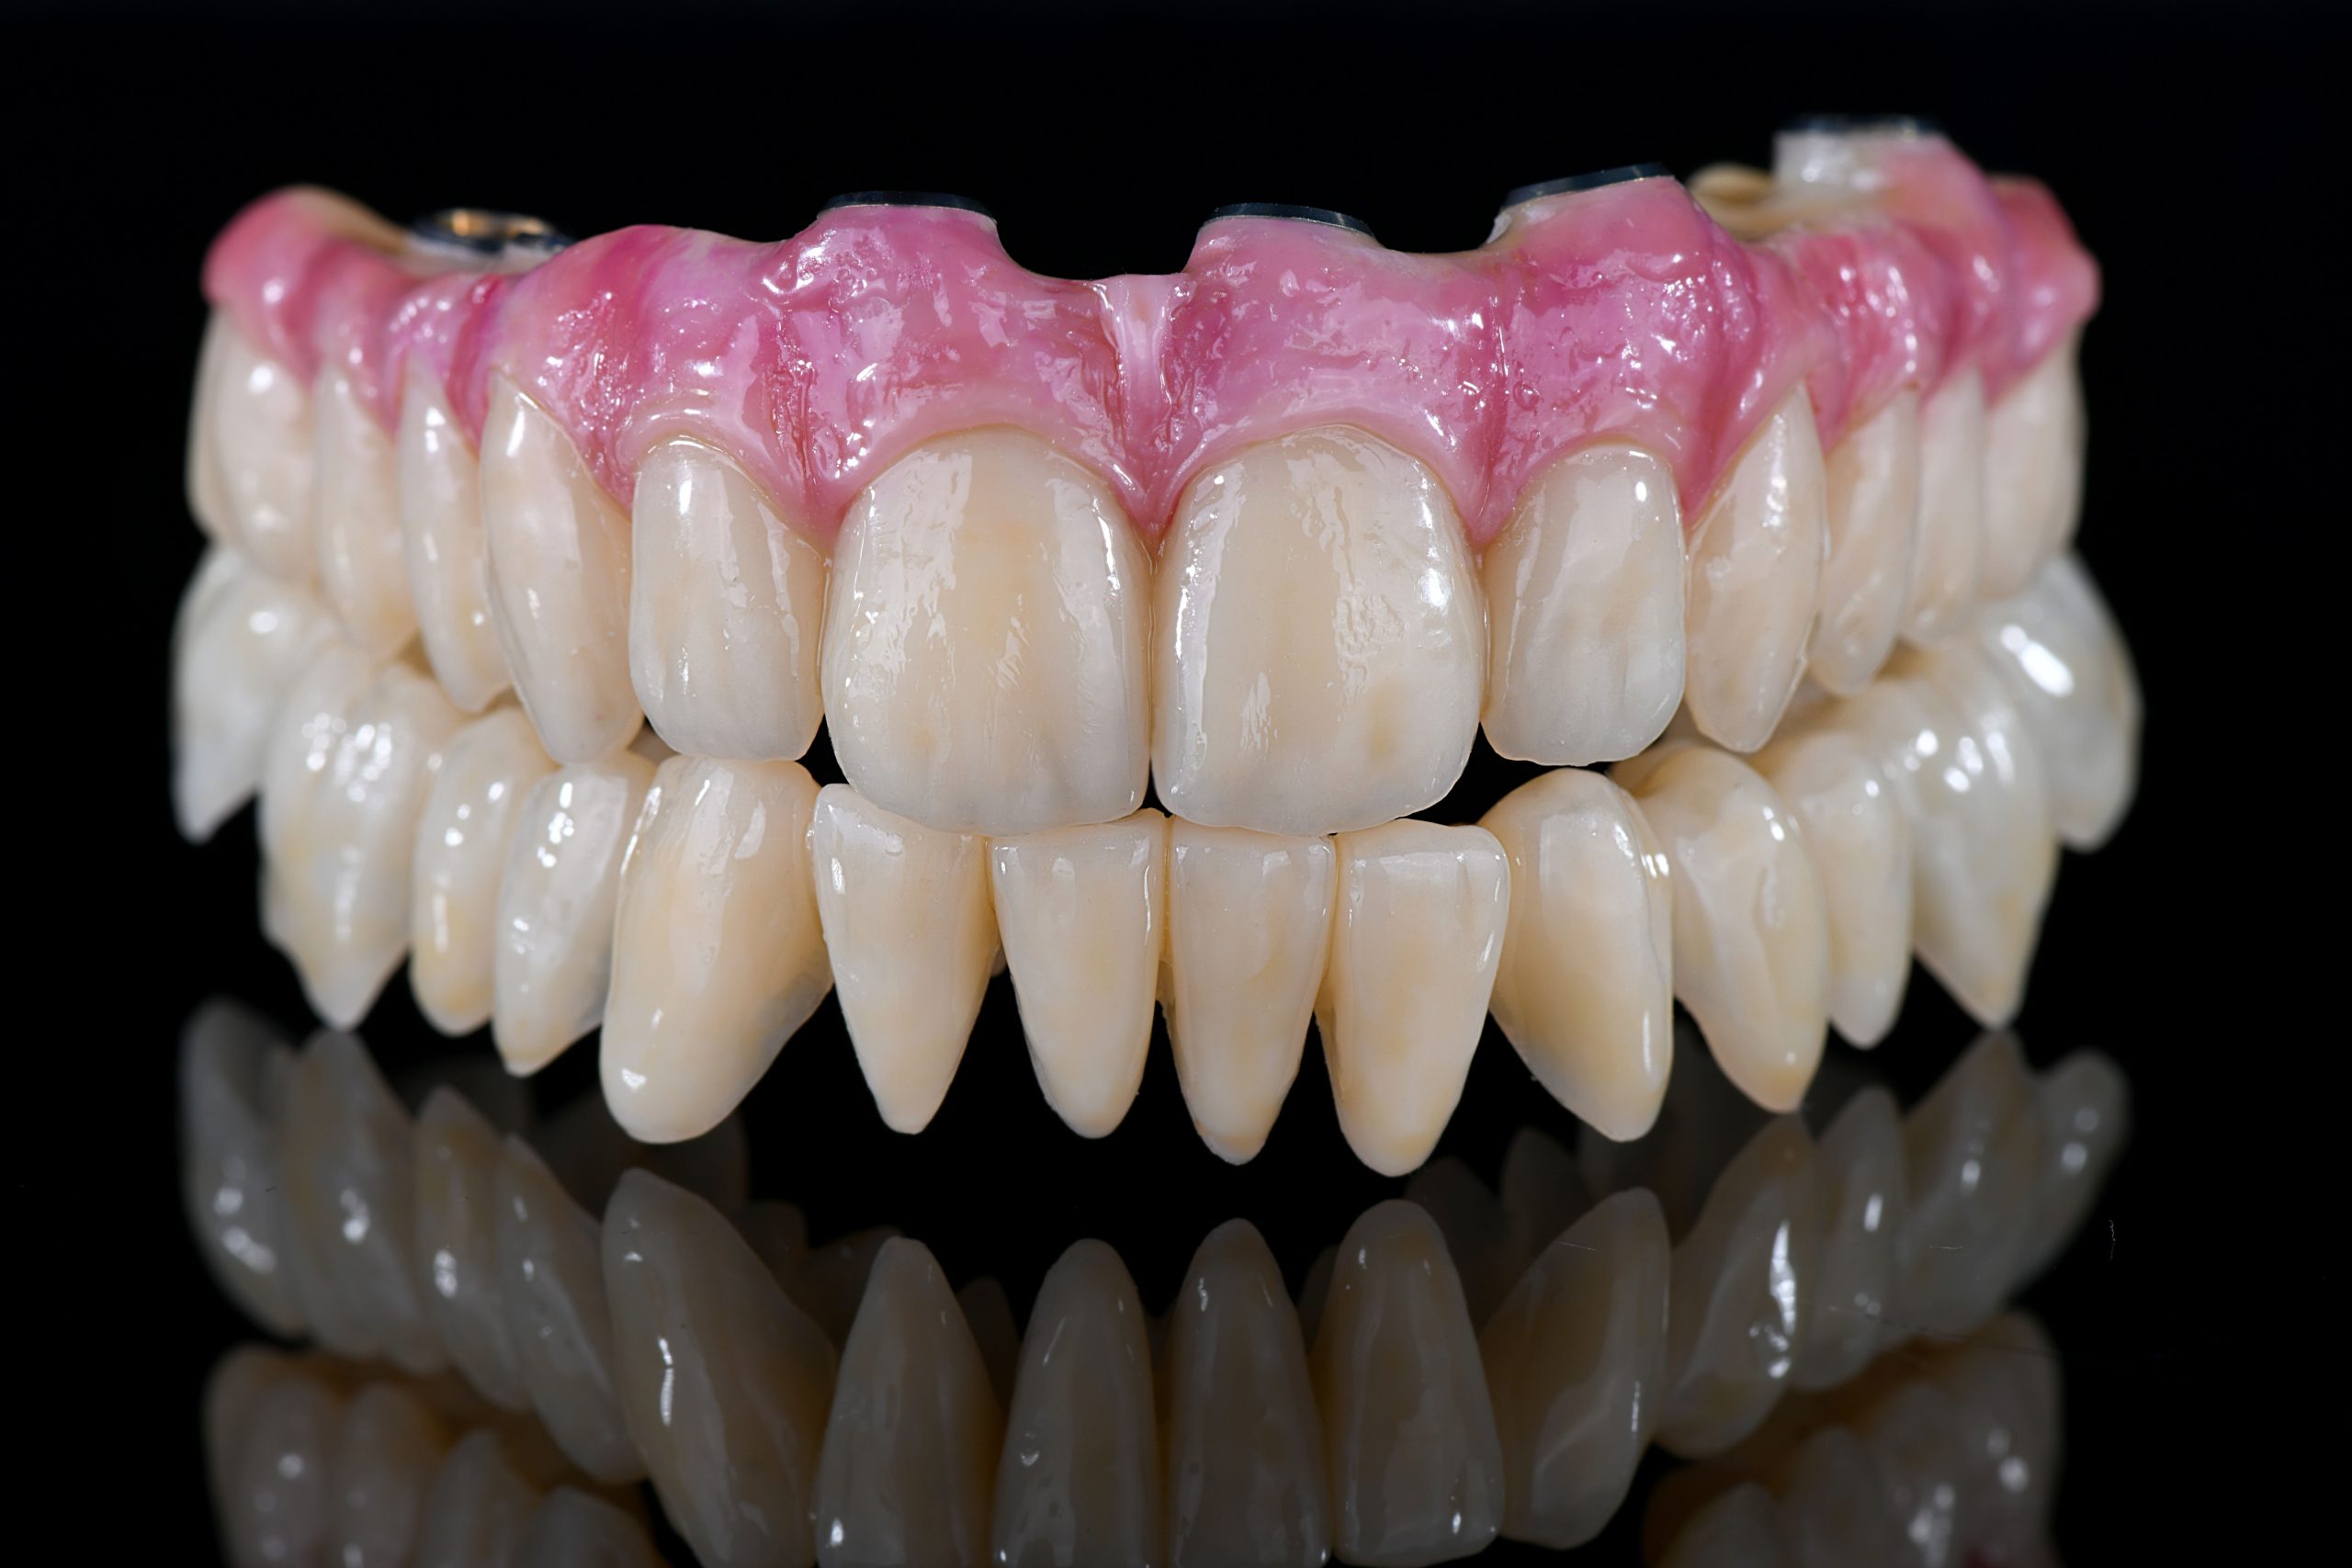

Complete Digital Patient (CDP): the use of guided surgery for implant restoration in total upper and lower rehabilitation with titanium bars and different types of zirconia-ceramic

Full upper and lower rehabilitation with titanium and zirconia bars

Upper and lower prosthetic rehabilitation with titanium bars and translucent zirconia-ceramic structures. The CDP as an aid in communication between the entire team and the patient, who is the focus of the work.